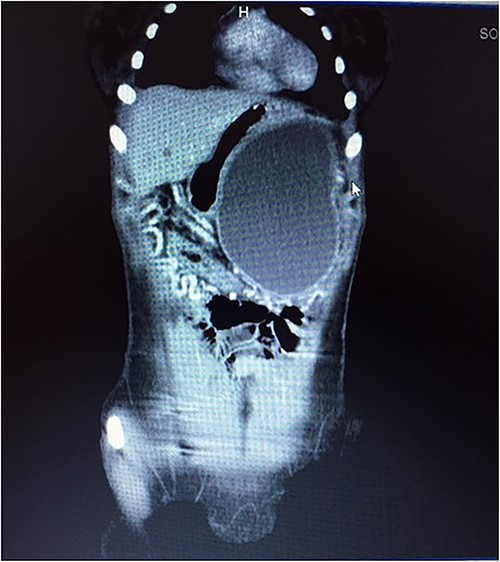

A 14-year-old female with no relevant past medical history presented with a 2-week history of right upper quadrant abdominal swelling. She gave no history of trauma, pain, fever, jaundice, alteration in bowel habits, early satiety, bloating, or anorexia. On physical examination, she appeared healthy. Her vital signs were normal, and she was anicteric. The rest of her exam was normal except for a right upper quadrant fullness and a palpable liver edge 6 cm below the right costal margin. An abdominal ultrasound was interpreted as a right lobe liver mass. A fine needle aspirate revealed necrotic tissue with no hepatocytes seen. A thoraco-abdominal CT scan revealed an enhancing, centrally necrotic retroperitoneal mass of 9 × 12 cm compressing the duodenum, portal vein, and inferior vena cava. Mild adjacent free fluid was noted. There was no evidence of metastatic disease (Fig. 1). All routine blood tests including complete blood count, chemistries (amylase and lipase inclusive) and coagulation studies were normal. A gastrointestinal stromal tumor was suspected.

A contrast-enhanced CT scans of the abdomen showing a large, well-defined, and heterogeneous tumor.